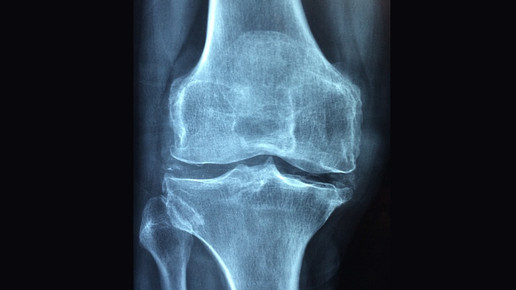

Als wäre eine Schuppenflechte nicht schon belastend genug, gesellen sich bei manchen Patienten auch noch Gelenkentzündungen dazu. Sie sollten schon in einem frühen Stadium mit entzündungshemmenden Mitteln behandelt werden, rät die ABDA. Die Gelenke können sonst dauerhaft Schaden nehmen.

Das Problem: Häufig erkennen die Patienten gar nicht, dass sie von Psoriasis-Arthritis betroffen sind. Ein Anzeichen ist den Apothekern zufolge, wenn einzelne Gelenke morgens steif sind. Auch wer regelmäßig mit einem oder mehreren „Wurstfingern“, geschwollenen Zehen, Ellenbogen, Knie- oder Sprunggelenken aufwacht, sollte mit dem Arzt darüber sprechen.